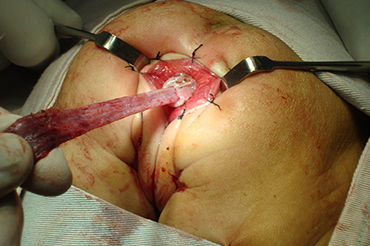

Enfermedad de Hirschsprung